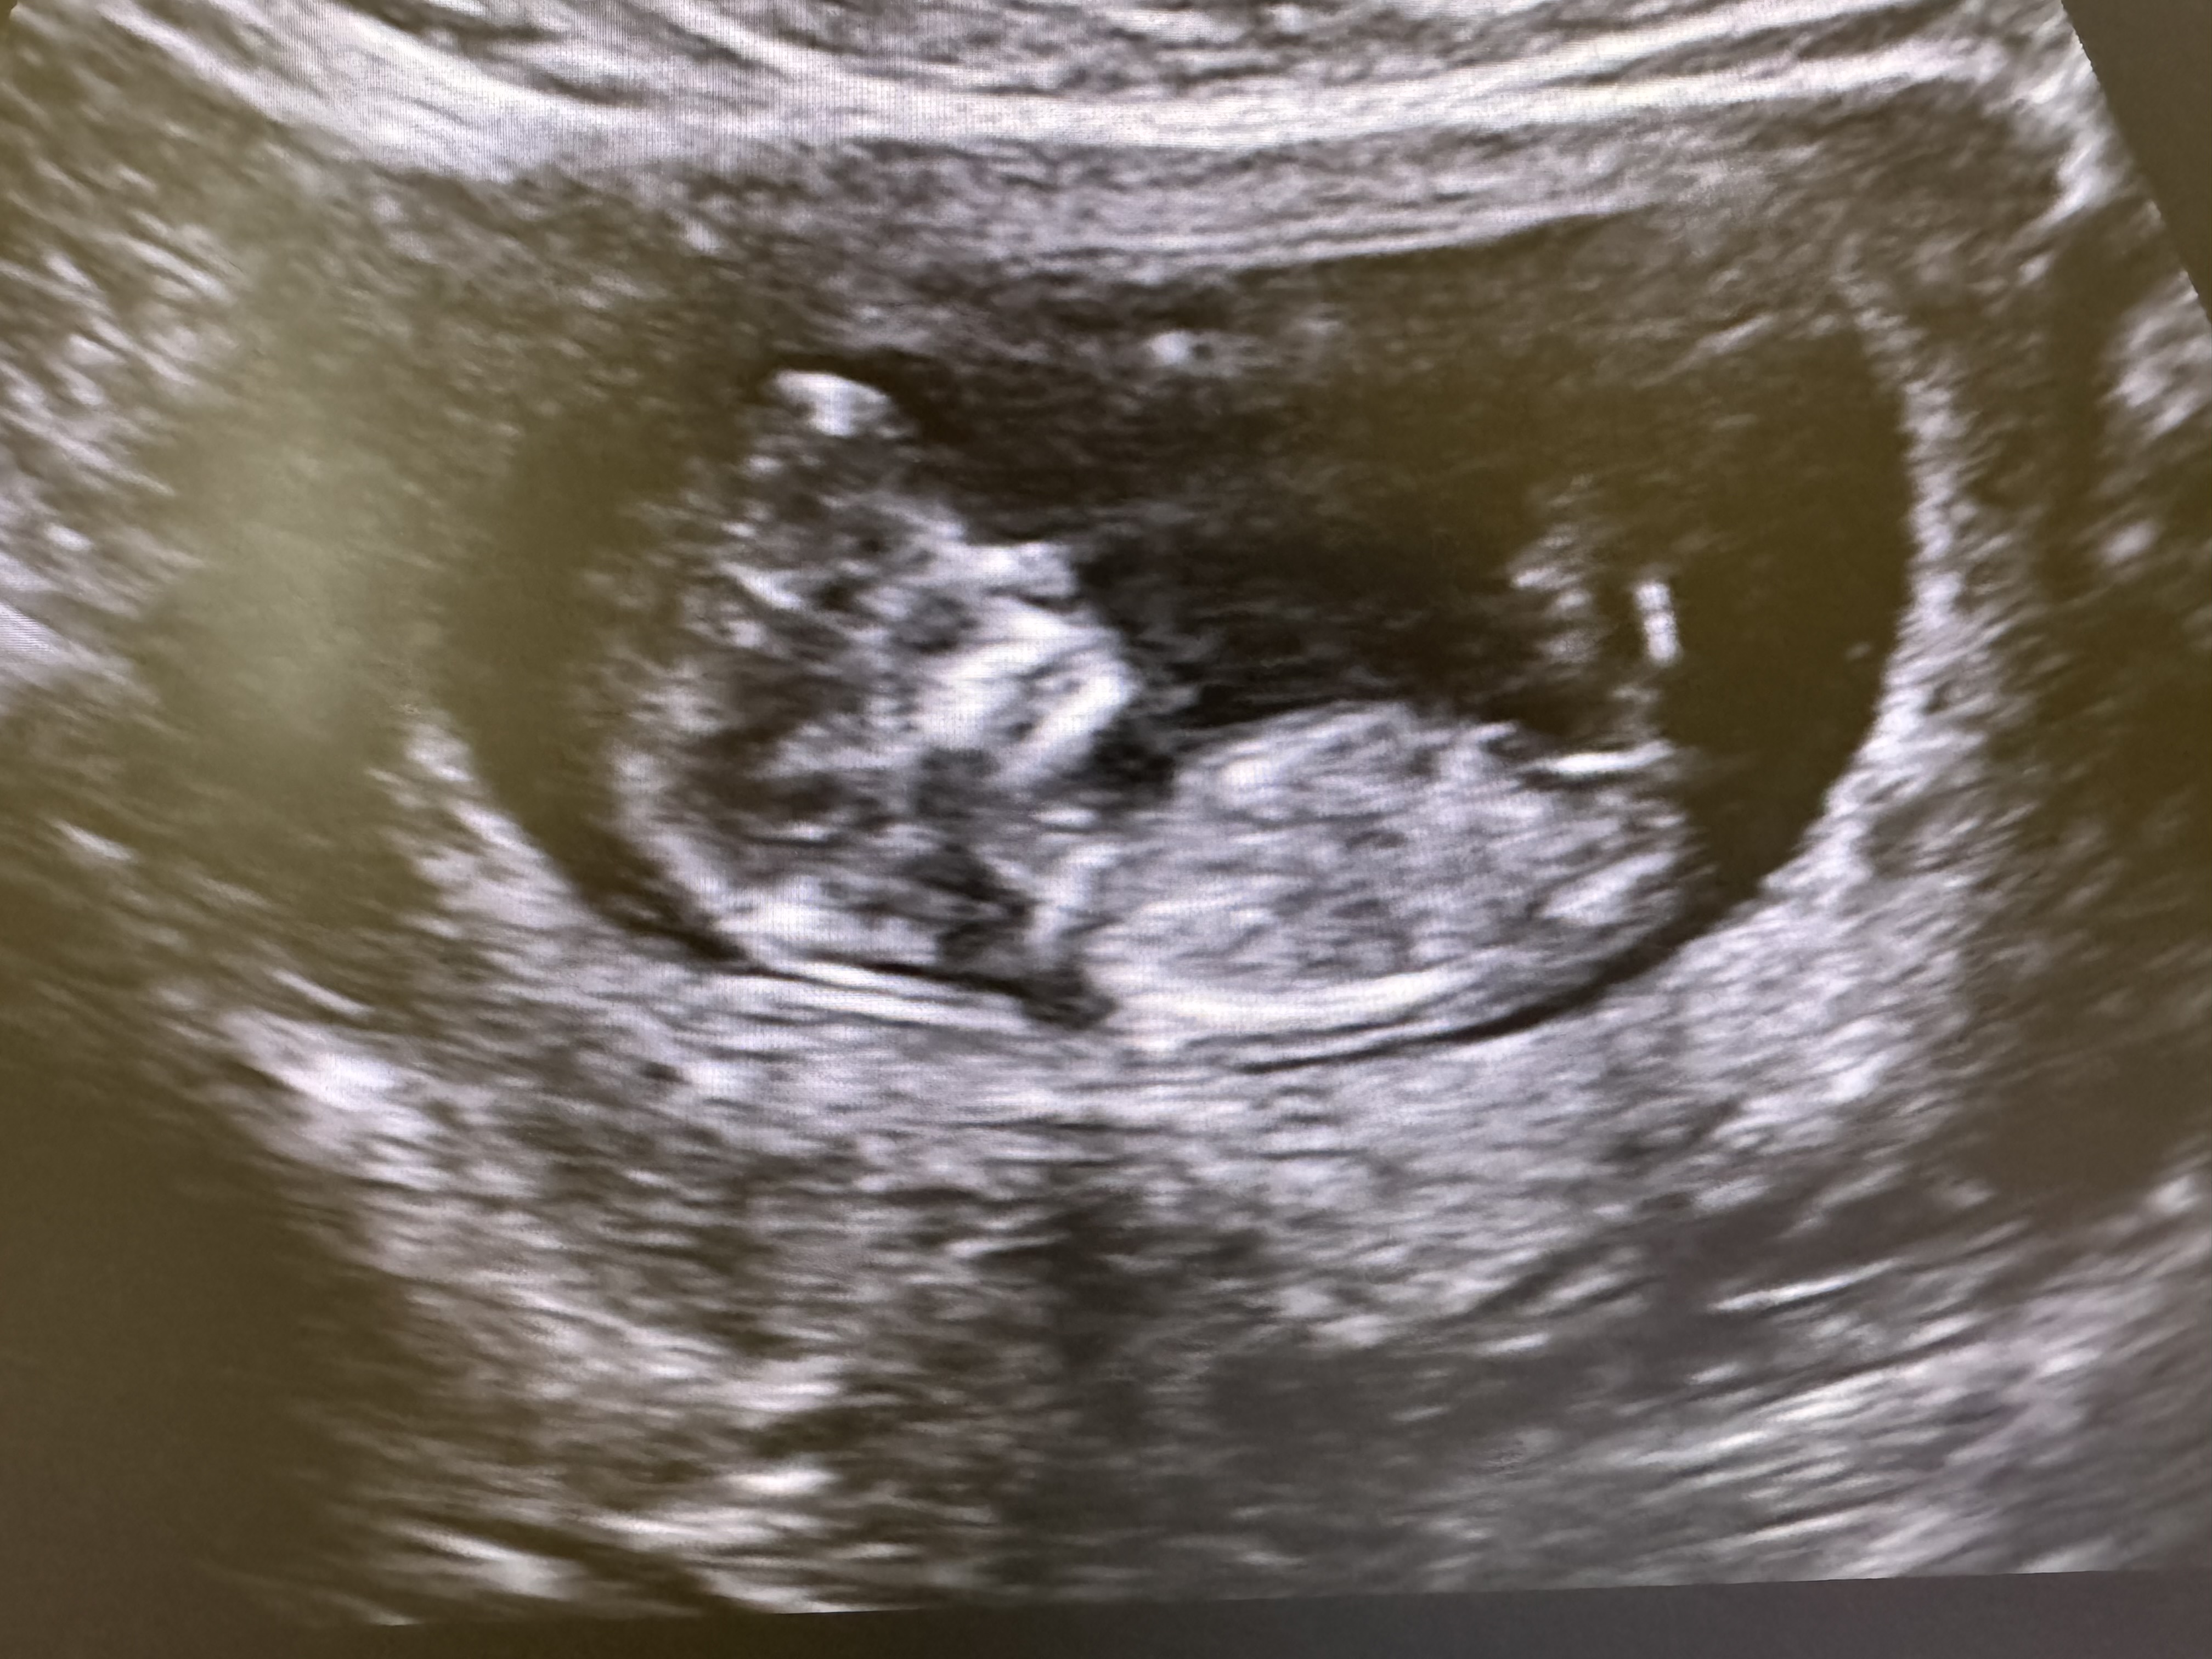

1й скрининг, интересно кто там

Вроде бы девчуля) первый Ваш малыш? Пусть беременность протекает благополучно💖🙌🏼

Девчуля)

Мне видится дама)

видно не очень, но я бы предположила девочку)

Девочка

Мне кажется, девочка ❤️

Не видно, он же бочком лежит, еще очень рано, я ближе к неделям 16 пойду узнавать как малыш и как раз скажут пол наверное

Ольга, половой бугорок параллельно позвоночнику, с мальчиками он перпендикулярно. Но, ждём результатов от автора)

Диана, ну вот белая полоска параллельно позвоночнику 😄 около ножек